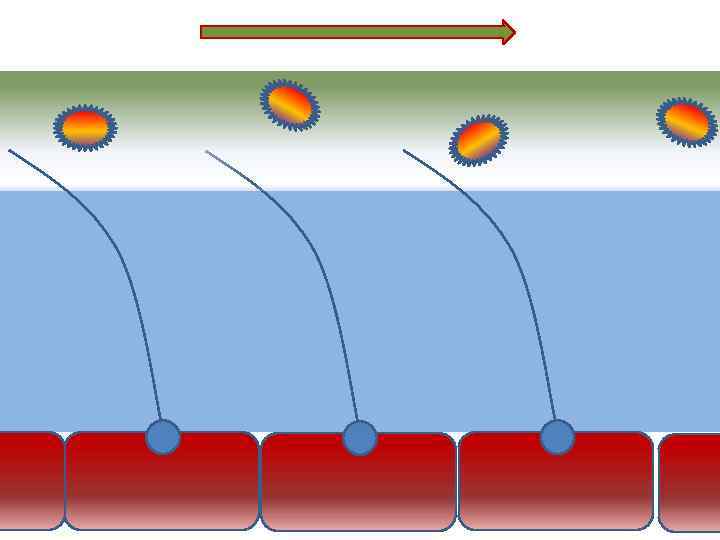

Оптимальное увлажнение Достаточная продукция слизи Хороший транспорт Экономит энергию и воду Защитная функция

Оптимальное увлажнение Достаточная продукция слизи Хороший транспорт Экономит энергию и воду Защитная функция

Механизм защиты легкого Слизь (зеленый цвет) нейтрализует и связывает патогенную флору(синий цвет) Слизь – это барьер между клетками и патогенной флорой Слизь – это транспортное средство

Механизм защиты легкого Слизь (зеленый цвет) нейтрализует и связывает патогенную флору(синий цвет) Слизь – это барьер между клетками и патогенной флорой Слизь – это транспортное средство

Нормальное состояние слизистого бронхиального секрета возможно только при 100% относительной влажности воздуха

Нормальное состояние слизистого бронхиального секрета возможно только при 100% относительной влажности воздуха

Факторы риска Недостаточное увлажнение дыхательной смеси Высушивание трахеи и бронхов

Факторы риска Недостаточное увлажнение дыхательной смеси Высушивание трахеи и бронхов

Плохое увлажнение • Вязкая слизь - потеря ресничек • Высушивание слизистой смерть клеток • Высушивание слизи в бронхиолах-ателектазы • Затраты энергии на согревание воздуха • Затраты воды на увлажнение

Плохое увлажнение • Вязкая слизь - потеря ресничек • Высушивание слизистой смерть клеток • Высушивание слизи в бронхиолах-ателектазы • Затраты энергии на согревание воздуха • Затраты воды на увлажнение